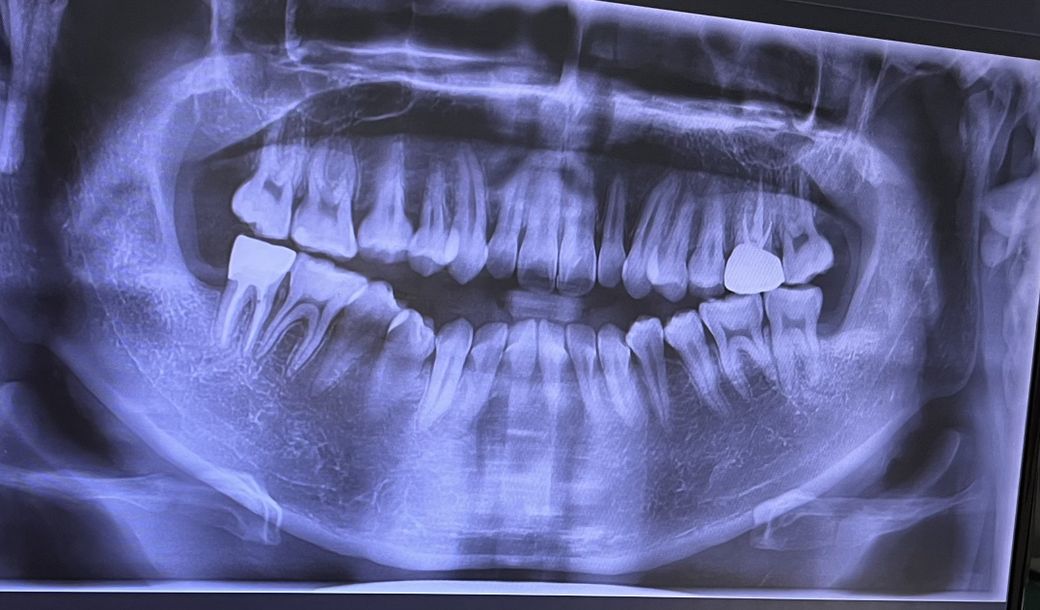

혹시 이빨마모가 많이 된건가요?

현재 개방교합때문에 교정중이고요 잘때 가끔씩 이갈이를 합니다. 근데 교정중에 이갈이가 굉장히 안좋을 것 같고 치아마모가 심각하게 진행된건지 궁금해서 글 올립니다. 상세한 답변 부탁드립니다 !

파노라마 사진만으로는 마모의 정도를 정확하게 파악하기 힘드나 대구치의 치아의 cups가 뭉툭해 진것으로 봤을 경우 이갈이를 통한 치아 마모가 어느정도 진행되어 있을을 예상해 볼수 있습니다.

사진 상으로는 치아마모가 심하게 진행된 상태는 아닙니다. 단, 경미한 마모의 경우에는 방사선 사진 및 파노라마 사진으로는 알 수 없으며 임상 사진도 같이 보아야 합니다. 파노라마 사진 상에 마모가 보일 정도라면 엄청 심한 마모이며 지금 파노라마 사진으로서는 마모의 흔적이 많지 않습니다.